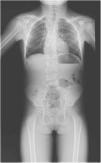

En el estudio radiológico (fig. 1), la resonancia magnética de columna (fig. 2) y el panel de secuenciación masiva de displasias esqueléticas (463 genes) se encontraron 2 variantes en heterocigosis compuesta, NM_016941.3:c.[988G>T];[1312T>C], p.[(Gly330Cys)];[(Cys438Arg)], en el gen DLL3. Ambos padres eran portadores de una de las variantes. Ambas fueron clasificadas como de significado incierto por el American College of Medical Geneticists.

RNM columna en proyección coronal y sagital (7 años y 10 meses). Segmento cervical: rectificación de la lordosis cervical fisiológica. Segmento dorsal: 9 pares de costillas. Hemivértebra derecha en D3 y D5-D6. D8-D9 con 2 hemivértebras. D10 hemivértebra rudimientaria. Ausencia de D11 y D12.